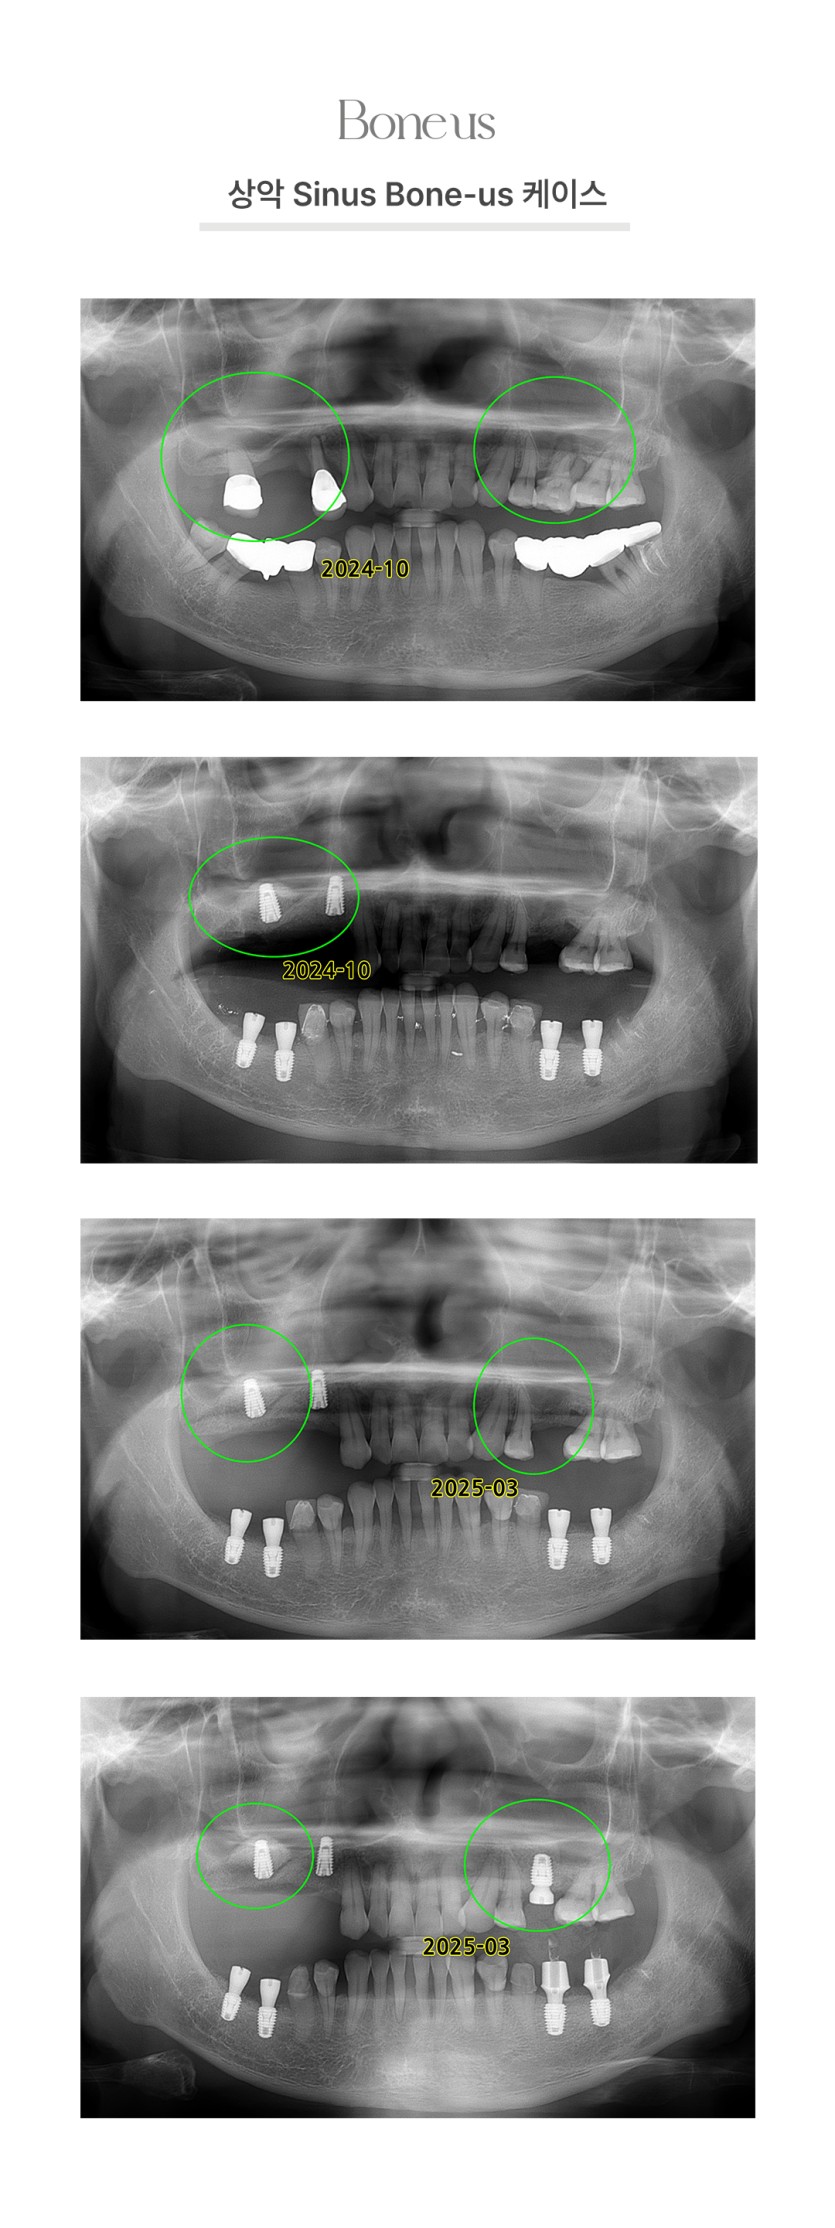

상악 Sinus 본어스 케이스 2